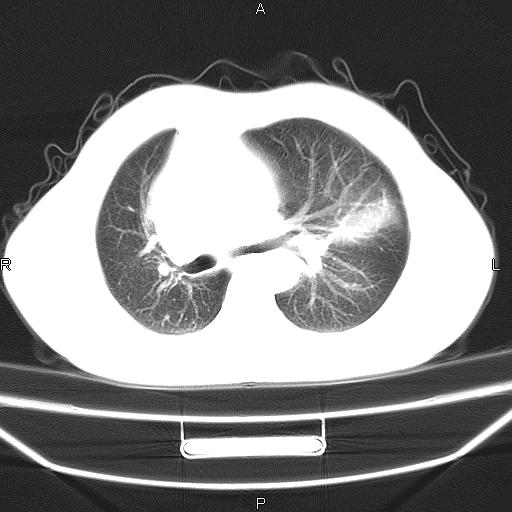

患者,男。50岁。近几日有咳嗽症状,无其他不适,既往病史无,考虑膈疝。请前辈们看看指导指导。

膈膨升,左下肺通气不良,膈肌好像还完整。

符合隔膨升,膈肌较完整。